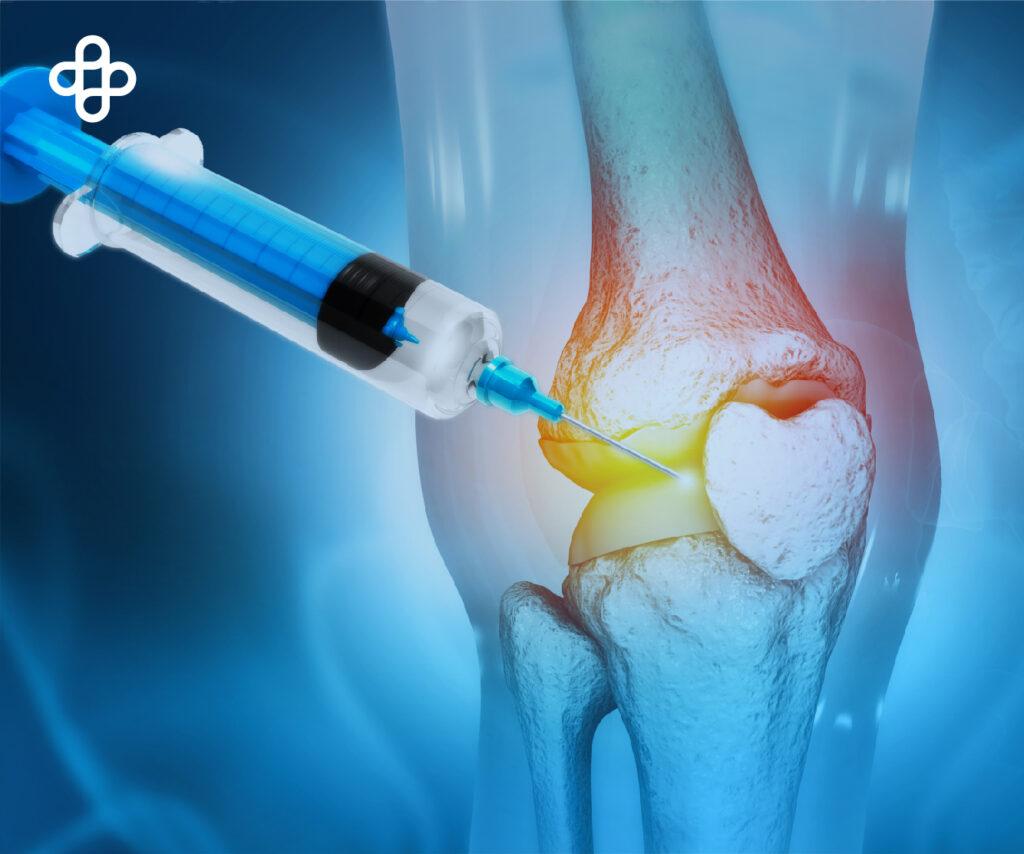

Players of Life reconoce al Centro Médico Eternal y al Dr. Juan Garza por sus 35 años de experiencia y 15,000 pacientes tratados con medicina regenerativa en México.